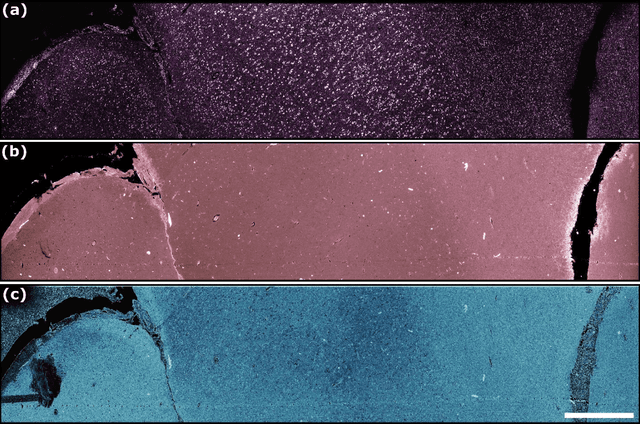

Abstract:Modern histopathology relies on the microscopic examination of thin tissue sections stained with histochemical techniques, typically using brightfield or fluorescence microscopy. However, the staining of samples can permanently alter their chemistry and structure, meaning an individual tissue section must be prepared for each desired staining contrast. This not only consumes valuable tissue samples but also introduces delays in essential diagnostic timelines. In this work, virtual histochemical staining is developed using label-free photon absorption remote sensing (PARS) microscopy. We present a method that generates virtually stained histology images that are indistinguishable from the gold standard hematoxylin and eosin (H&E) staining. First, PARS label-free ultraviolet absorption images are captured directly within unstained tissue specimens. The radiative and non-radiative absorption images are then preprocessed, and virtually stained through the presented pathway. The preprocessing pipeline features a self-supervised Noise2Void denoising convolutional neural network (CNN) as well as a novel algorithm for pixel-level mechanical scanning error correction. These developments significantly enhance the recovery of sub-micron tissue structures, such as nucleoli location and chromatin distribution. Finally, we used a cycle-consistent generative adversarial network CycleGAN architecture to virtually stain the preprocessed PARS data. Virtual staining is applied to thin unstained sections of malignant human skin and breast tissue samples. Clinically relevant details are revealed, with comparable contrast and quality to gold standard H&E-stained images. This work represents a crucial step to deploying label-free microscopy as an alternative to standard histopathology techniques.

Abstract:The field of histology relies heavily on antiquated tissue processing and staining techniques that limit the efficiency of pathologic diagnoses of cancer and other diseases. Current staining and advanced labeling methods are often destructive and mutually incompatible, requiring new tissue sections for each stain. This prolongs the diagnostic process and depletes valuable biopsy samples. In this study, we present an alternative label-free histology platform using the first transmission-mode Photon Absorption Remote Sensing microscope. Optimized for automated whole slide scanning of unstained tissue samples, the system provides slide images at magnifications up to 40x that are fully compatible with existing digital pathology tools. The scans capture high quality and high-resolution images with subcellular diagnostic detail. After imaging, samples remain suitable for histochemical, immunohistochemical, and other staining techniques. Scattering and absorption (radiative and non-radiative) contrasts are shown in whole slide images of malignant human breast and skin tissues samples. Clinically relevant features are highlighted, and close correspondence and analogous contrast is demonstrated with one-to-one gold standard H&E stained images. Our previously reported pix2pix virtual staining model is applied to an entire whole slide image, showcasing the potential of this approach in whole slide label-free H&E emulation. This work is a critical advance for integrating label-free optical methods into standard histopathology workflows, both enhancing diagnostic efficiency, and broadening the number of stains that can be applied while preserving valuable tissue samples.

Abstract:Significance: Histopathological analysis of tissues is an essential tool for grading, staging, diagnosing and resecting cancers and other malignancies. Current histopathological techniques require substantial sample processing prior to staining with hematoxylin and eosin (H&E) dyes, to highlight nuclear and cellular morphology. Sample preparation and staining is resource-intensive and introduces potential for variability during sample preparation. Aim: We present a novel method for direct label-free histopathological assessment of formalin fixed paraffin embedded tissue blocks and thin tissue sections using a dual contrast photoacoustic remote sensing (PARS) microscopy system. Approach: To emulate the nuclear and cellular contrast of H&E staining, we leverage unique properties of the PARS system. Here the ultraviolet excitation of the PAARS microscope takes advantage of DNA's unique optical absorption to provide nuclear contrast analogous to hematoxylin staining of cell nucelli. Concurrently, the optical scattering contrast of the PARS detection system is leveraged to provide bulk tissue contrast analogous to eosin staining of cell membranes. Results: We demonstrate the efficacy of this technique by imaging human breast tissue and human skin tissues in formalin fixed paraffin embedded tissue blocks and frozen sections respectively. Salient nuclear and extra-nuclear features such as cancerous cells, glands and ducts, adipocytes, and stromal structures such as collagen. Conclusions. The presented dual contrast PARS microscope enables label-free visualizations of tissue with contrast and quality analogous to the current gold standard for histopathological analysis. Thus, the proposed system is well positioned to augment existing histopathological workflows, providing histological imaging directly on unstained tissue blocks and sections.